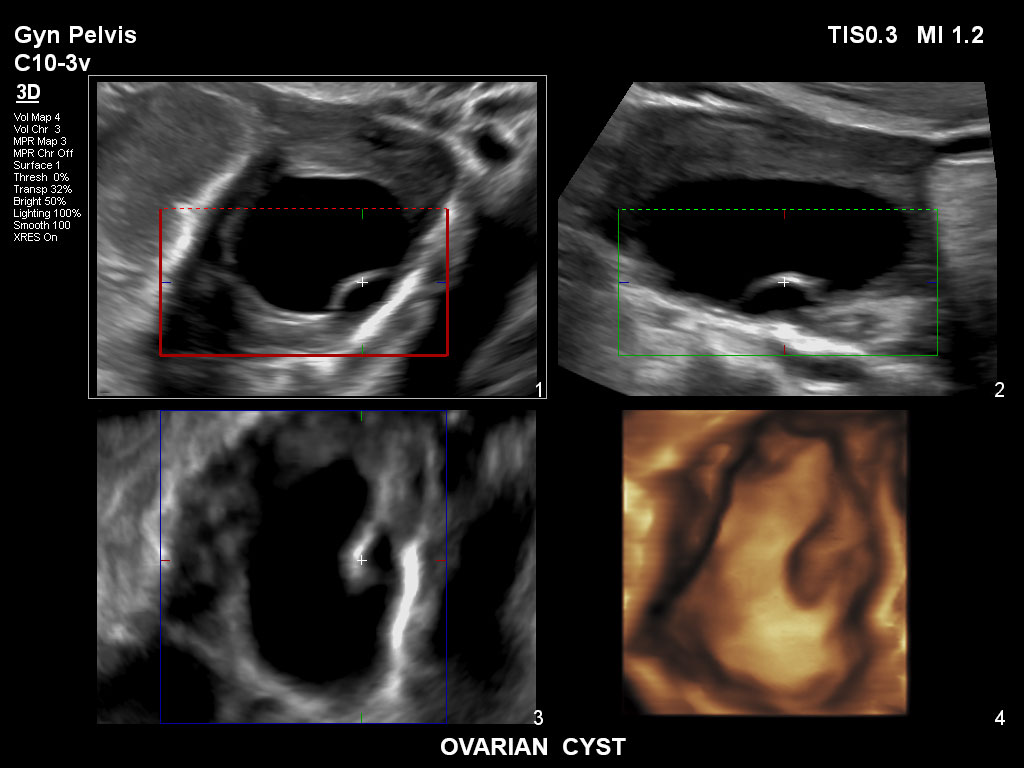

• C10-3v PureWave-Breitband-Endo-Convex-Schallkopf, ideal für anspruchsvolle Myom- und komplexe Ovar-Untersuchungen sowie Bildgebung im ersten Schwangerschaftstrimester